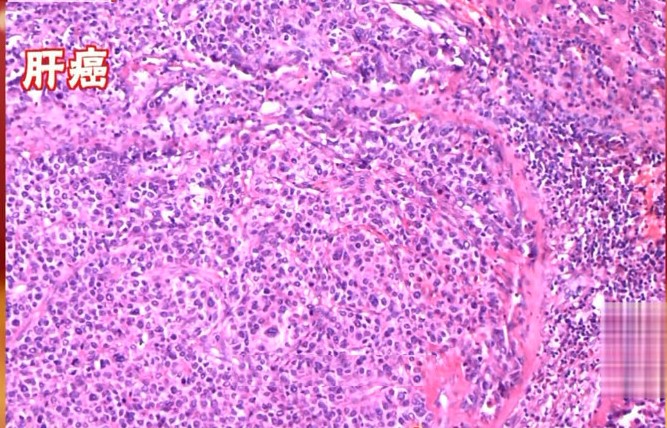

5)肝癌

在进一步恶化发展成肝癌,肝癌的发生并不一定会遵循这四步过程,在肝病变恶化的过程中,每一步都可以直接进入到肝癌。

肝脏癌变可能会超近道,在肝脏不断损害修复的过程中,出现修复障碍,比如癌细胞的突变,都可能直接进入肝癌。